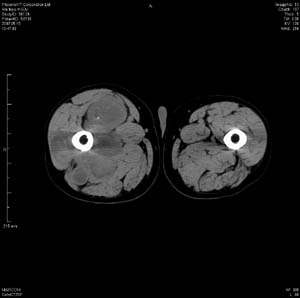

男 63岁 右大腿无痛性肿块11年,x片右大腿软组织肿块影,余无明显异常.ct值-13__239hu

右大腿股内侧股与收肌间隙间多发囊实性占位,界清.内示斑点状钙化.局部骨质无异常.肌肉推压移位表现.

考虑肌间隙病变.可有1,神经来源肿瘤.2,血管来源病变.3,淋巴来源肿瘤.4,脂肪来源肿瘤.5,滑膜来源肿瘤.结合病史只能考虑良性占位.建议增强或mri进一步分析.

同意,病史较长,病变周围分界清晰,考虑良性病变。病灶内有多发斑点状钙化,沿肌间隙生长,血管瘤或淋巴管瘤首先考虑。